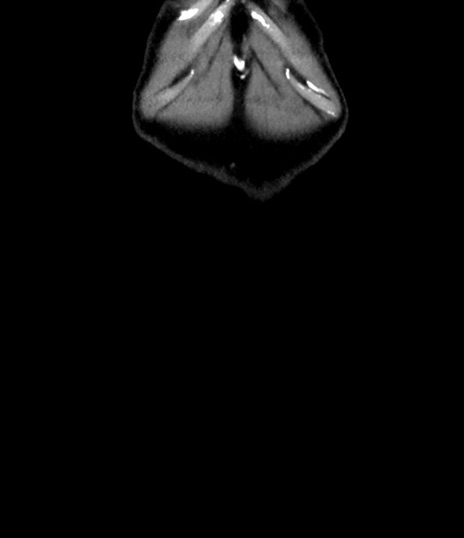

横断像

【症例】 60歳代男性

【主訴】 黒色吐物

【現病歴】 4日前から嘔気自覚、2日前の朝食後にも嘔気あり、自分で手で嘔吐反射起こし嘔吐したところ血が混ざっていたため受診。

【既往歴】 5年前汎発性腹膜炎を伴う急性虫垂炎で手術、高血圧、前立腺肥大症、高脂血症

【身体所見】 腹部正中に手術癩痕あり 腹部平坦・軟圧痛なし膨満感あり

【データ】WBC 8400、CRP 4.54